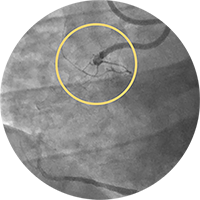

Внутристентовый рестеноз в левой передней нисходящей артерии: ко-регистрация данных с iFR и ВСУЗИ, лазерная атерэктомия, использование баллона с лекарственным покрытием и стентирование.

Внутристентовый рестеноз в огибающей артерии: ко-регистрация с ВСУЗИ, баллонный моделирующий катетер, терапия с помощью баллона с лекарственным покрытием под контролем ВСУЗИ.

Изображение предоставил Аллен Джеремайас, врач. На изображении показано программное обеспечение SyncVision с функцией обнаружения устройств, которое позволяет легко визуализировать особенности проведения терапии.